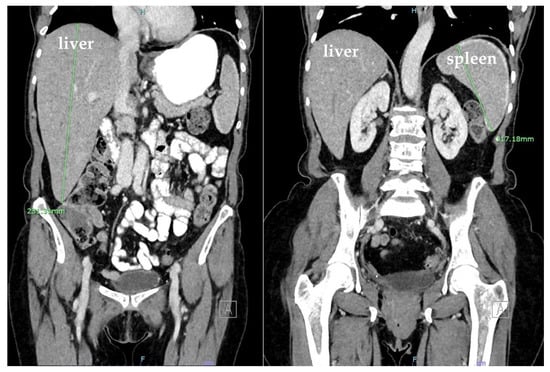

Computed tomography (CT) of the abdomen and pelvis revealed hepatomegaly of 23 cm with no other acute findings (Figure 2). During hospitalization, hemoglobin dropped to 6.1 g/dL, requiring transfusion of a unit of packed RBC, which improved hemoglobin to 7.0 g/dL. The nausea and vomiting persisted, warranting a repeat CT of the abdomen and pelvis, which showed new development of hemoperitoneum in the left abdomen surrounding the spleen, leading to concerns about subcapsular hematoma and an enlarged spleen by 13.2 cm (Figure 3). Additionally, the patient developed dyspnea, and chest X-ray revealed a pleural effusion in the left lung base.

Figure 2. Coronal plane computed tomography (CT) scan with IV contrast of the abdomen and pelvis showing hepatomegaly (23 cm). Spleen was normal.

Figure 3. Coronal and sagittal plane computed tomography (CT) scans with IV contrast of the abdomen and pelvis showing hemoperitoneum (white arrows) and mild splenomegaly (13.2 cm).